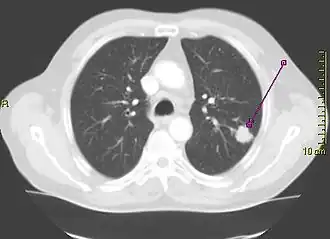

A person suspected of having lung cancer will have imaging tests done to evaluate the presence, extent, and location of tumors. First, many primary care providers perform a chest X-ray to look for a mass inside the lung.[9] The X-ray may reveal an obvious mass, the widening of the mediastinum (suggestive of spread to lymph nodes there), atelectasis (lung collapse), consolidation (pneumonia), or pleural effusion;[10] however, some lung tumors are not visible by X-ray.[6] Next, many undergo computed tomography (CT) scanning, which can reveal the sizes and locations of tumors.[9][11]

A definitive diagnosis of lung cancer requires a biopsy of the suspected tissue be histologically examined for cancer cells.[12] Given the location of lung cancer tumors, biopsies can often be obtained by minimally invasive techniques: a fiberoptic bronchoscope that can retrieve tissue (sometimes guided by endobronchial ultrasound), fine needle aspiration, or other imaging-guided biopsy through the skin.[12] Those who cannot undergo a typical biopsy procedure may instead have a liquid biopsy taken (that is, a sample of some body fluid) which may contain circulating tumor DNA that can be detected.[13]

Lung cancer can often appear as a solitary pulmonary nodule on a chest radiograph or CT scan. In lung cancer screening studies as many as 30% of those screened have a lung nodule, the majority of which turn out to be benign.[16] Besides lung cancer many other diseases can also give this appearance, including hamartomas, and infectious granulomas caused by tuberculosis, histoplasmosis, or coccidioidomycosis.[17]